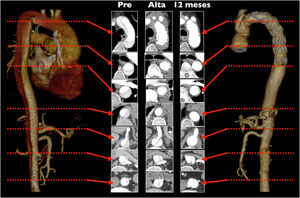

Aunque no existe evidencia de peso, diversos estudios observacionales sugieren un beneficio en términos de supervivencia y reintervención sobre la aorta distal en los pacientes con SAA en los que se realiza un tratamiento agresivo sobre el arco aórtico67-70. El mecanismo sugerido se deriva de una mayor incidencia de trombosis de la falsa luz en la aorta distal frente al tratamiento convencional, y por ello, menor crecimiento de la misma71,72. En torno al 90% de los pacientes presentan trombosis de la falsa luz a nivel de la endoprótesis, y del 60 al 70% a nivel de la aorta torácica descendente distal. El máximo beneficio se produce en aquellos pacientes con mayor riesgo de dilatación de la falsa luz en el seguimiento, que son los jóvenes, los portadores de colagenopatías y aquellos con reentradas a nivel del cayado aórtico, troncos supraaórticos y aorta torácica descendente (fig. 10)19,73,74. Como se ha señalado ya, es muy importante la selección del tamaño adecuado del stent. Un stent demasiado pequeño puede llevar al cierre inadecuado de la entrada en la aorta descendente y a una menor tasa de trombosis de la falsa luz22,75-77. Por otro lado, un tamaño demasiado grande aumenta la incidencia de dSINE, y con ello hay un mayor riesgo no solo de malperfusión, sino también de dilatación de la luz verdadera distal en el seguimiento43. En series contemporáneas se estima una tasa de endofuga 1b menor al 5% y la tasa de dSINE en torno al 15% tras la FET78,79.